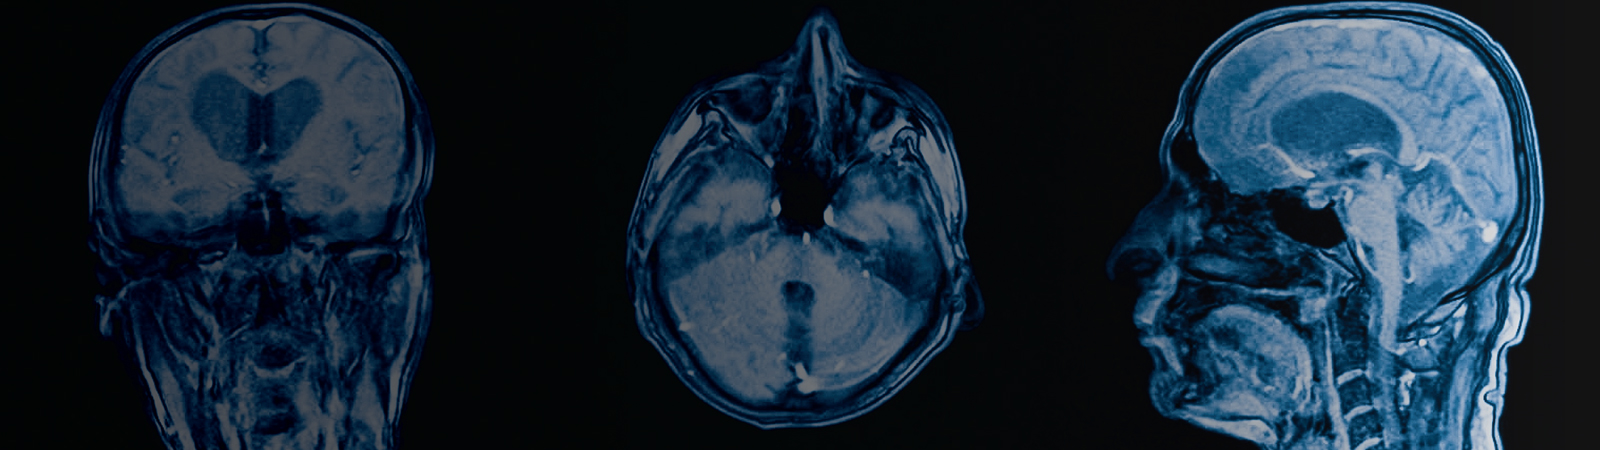

Neuro-Oncology

Brain and spinal tumors whether primary (arisinf from within the brain) or metastatic (coming from a remote source in the body).